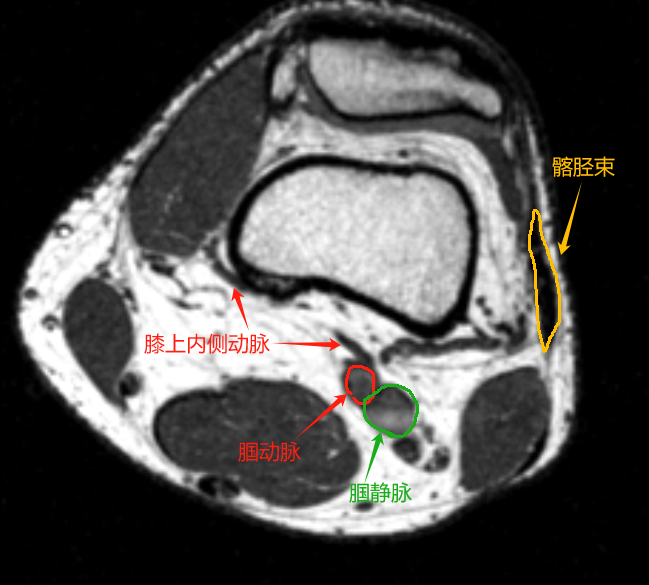

MRI断层解剖(膝关节)轴位为水平切面,从股骨远端至胫骨近端,重点显示以下结构:

1. 骨骼

• 股骨髁:后部圆形膨大,分为内侧髁(较大)和外侧髁(较小),关节面覆盖高信号的透明软骨。

• 胫骨平台:呈浅凹状,与股骨髁形成关节,边缘可见低信号的半月板。

2. 其他结构

• 髌下脂肪垫(Hoffa脂肪垫):髌腱后方的高信号脂肪组织。

• 滑膜皱襞:如内侧滑膜皱襞,轴位可见线状中等信号。